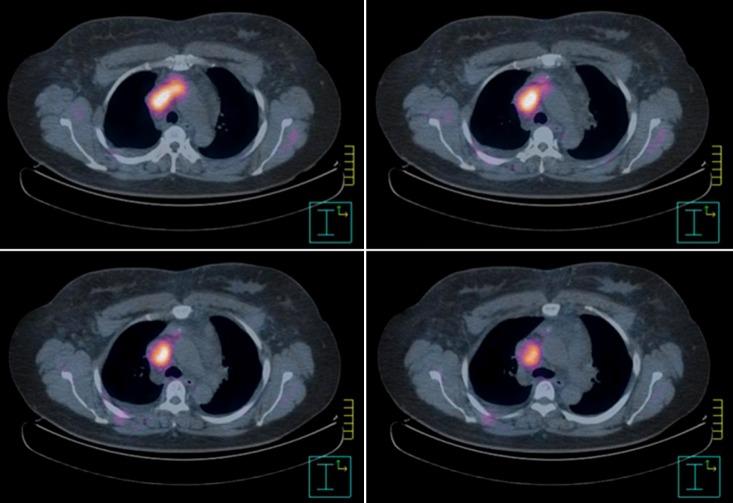

Superior vena cava syndrome (SVCS) is usually caused by extrinsic compression or invasion of the superior vena cava (SVC) by malignant tumors involving mediastinal structures. Although thymomas are well-known causes of SVCS, cases of SVCS caused by malignant thymomas protruding into adjacent vessels draining the SVC with thrombosis have been very rarely reported worldwide. We experienced a 39-year-old female patient with SVCS that developed after the direct invasion of the left brachiocephalic vein (LBCV) and SVC by an anterior mediastinal mass with a high maximum standardized uptake value on the chest computed tomography (CT) and positron emission tomography-CT. Based on these results, she underwent en bloc resection of the tumor, including removal of the involved vessels, and was eventually diagnosed as having a type B2 thymoma permeating into the LBCV and SVC. We present this case as a very rare form of SVCS caused by an invasive thymoma.

上腔静脉综合征(SVCS)通常是由涉及纵隔结构的恶性肿瘤对外侧上腔静脉(SVC)的外在压迫或侵犯所致。虽然胸腺瘤是SVCS的常见病因,但全球范围内,由恶性胸腺瘤突入引流SVC的相邻血管并伴有血栓形成导致SVCS的病例却鲜有报道。我们接诊了一名39岁的女性SVCS患者,该患者因前纵隔肿物直接侵犯左头臂静脉(LBCV)和SVC而发病,胸部计算机断层扫描(CT)及正电子发射断层扫描-CT显示该肿物的最大标准摄取值较高。基于这些检查结果,患者接受了肿瘤整块切除术,包括切除受累血管,最终被诊断为B2型胸腺瘤侵犯LBCV和SVC。我们将此病例作为侵袭性胸腺瘤导致的一种极为罕见的SVCS形式进行展示。